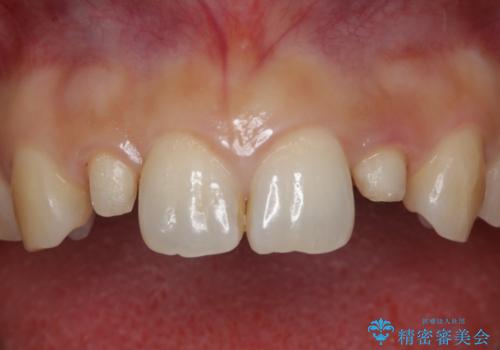

- 上の前歯が大きい事と下の前歯のがたつきを気にされてご相談にいらした方です。上の2番目の歯が矮小歯であったため、矯正治療にて歯のスペースを作った後、矮小歯には被せ物をして前歯のバランスを整えました。

歯科技工士さんとの打ち合わせを重ね、周囲の歯としっかりなじむ天然歯のような被せ物をお作りすることが出来ました。